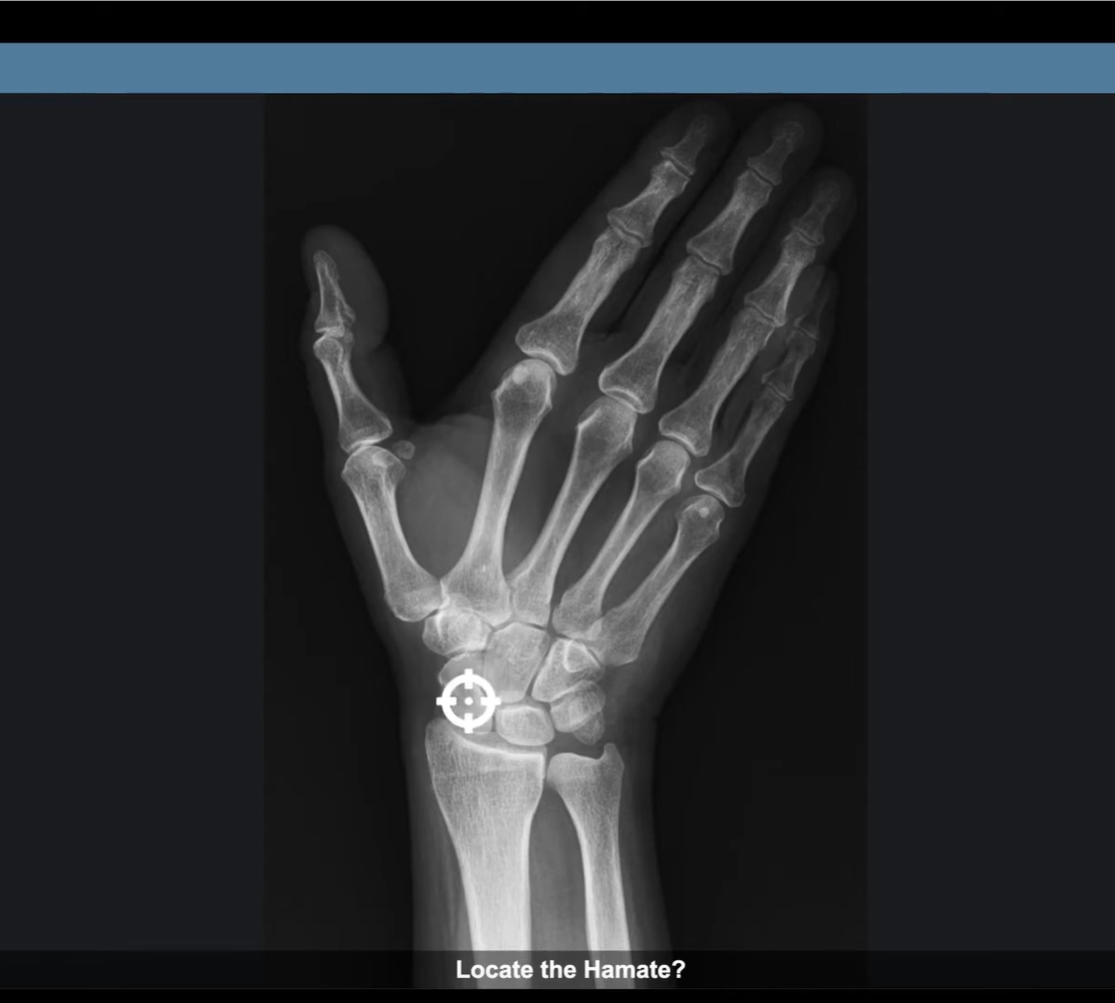

Review anatomy and practice collimation and positioning with these 30 interactive, online simulators. These web-based simulators will test your skills and help you learn with instant feedback. Challenge yourself to connect the dots between what you're learning in the classroom and what you'll encounter in a real-life clinical experience.

Each purchase allows one year of individual access to all 30 simulators. Nineteen simulators demonstrate radiographic, cross-sectional and surface anatomy from facial bones to limbs. Five simulators evaluate collimation and centering skills. Six simulators check for accurate positioning techniques.

Each purchase allows 60 days of individual access to all 30 simulators. Nineteen simulators demonstrate radiographic, cross-sectional and surface anatomy from facial bones to limbs. Five simulators evaluate collimation and centering skills. Six simulators check for accurate positioning techniques.